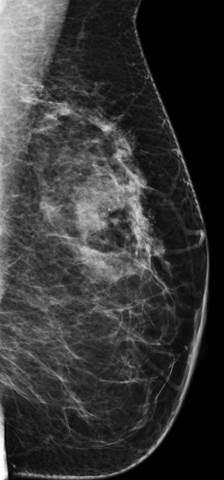

Ung thư vú

Ung thư vú - Ảnh 2

» Thông tin: Nữ giới – 42 tuổi.

» Lâm sàng: Kiểm tra sức khỏe.